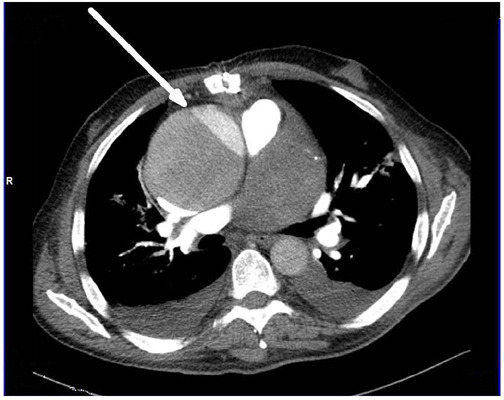

心脏手术后不久发生Stanford A型急性夹层的患者有很高的破裂和死亡风险。原发性升主动脉夹层(Stanford A型或De Bakey I型或II型)的表现、处理和结果都有很好的描述。然而,在心脏手术后不久(3-4周)发生Stanford A型急性主动脉夹层的患者有明显不同的表现、处理和术后结果。在本报告中,我们描述了一例早期Stanford a型急性主动脉夹层患者在初级冠状动脉搭桥术后四周的临床和手术表现。

Patients having Stanford type A acute dissection soon after cardiac surgery have a high risk of rupture and death. The presentation, management, and outcome of primary dissection of the ascending aorta (Stanford type A or De Bakey type I or II) are well described. However, patients with Stanford type A acute aortic dissection soon (3-4 weeks) after primary cardiac surgery have distinctly different presentation, management, and postoperative outcome. In this report, we describe the clinical and surgical findings of a patient with early Stanford type A acute aortic dissection four weeks after primary coronary artery bypass grafting.